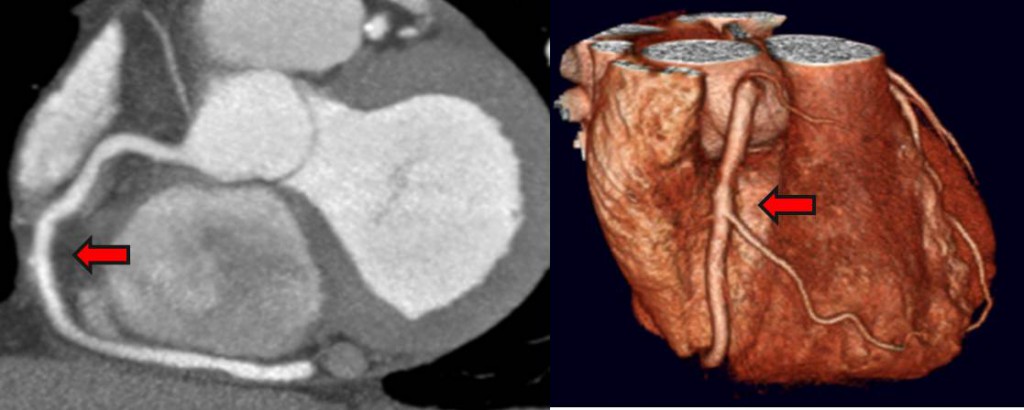

سی تی آنژیوگرافی قلب

سی تی آنژیو چیست؟